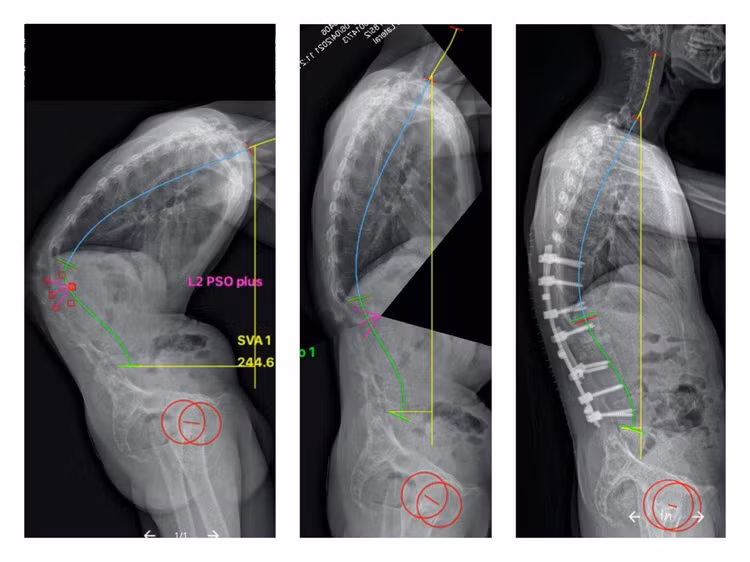

Hình X-quang cột sống của bệnh nhân trước mổ (hình bên trái), hình ảnh lên kế hoạch nắn chỉnh bằng phần mềm điện toán (hình giữa) và hình ảnh thực tế sau mổ của bệnh nhân (hình bên phải)

Bệnh nhân được lên kế hoạch mổ đục bỏ chân cung ở đốt L2, làm sạch ổ gãy L1/2, nắn chỉnh còng và cố định cột sống bằng ốc chân cung từ đốt sống ngực 10 đến đốt sống thắt lưng 5.

Việc lập kế hoạch nắn chỉnh hiện nay được hỗ trợ bởi các phần mềm điện toán chuyên dụng. Qua đó giúp xác định vị trí đục xương và mức độ đục xương tối ưu và dự đoán hình dáng cột sống sau phẫu thuật để phẫu thuật viên có thể điều chỉnh chiến lược nắn chỉnh cho phù hợp.

Kết quả lâm sàng và hình ảnh học của cả bốn bệnh nhân đều rất tốt, trong đó trường hợp vừa nêu là ca mổ có mức độ nắn chỉnh cao nhất, phục hồi được 66o còng.